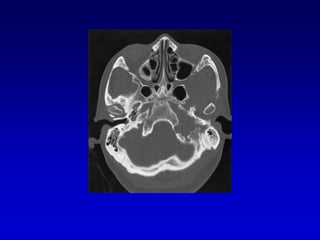

Caso 2TAC-RM

Caso 3TAC RM ANGIO